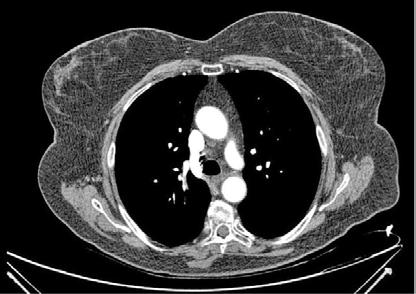

Se realizó una tomografía computarizada (TC) con contraste de forma emergente, que mostró una disección aórtica iatrogénica tipo A focal de origen en la zona 0 del cayado con extensión al tronco braquiocefálico derecho (1) sin afectar al resto de troncos supra-aórticos, cayado o aorta descendente (Figuras 1 y 2); además del hematoma

Figuras 1 y 2: Prótesis aórtica migrada y disección aórtica focal tipo A, de origen en la curvatura menor del arco aórtico (zona 0) hasta la bifurcación de la arteria braquiocefálica derecha; sin afectación de del resto de troncos supra-aórticos, del resto del cayado aórtico o de la aorta descendente.